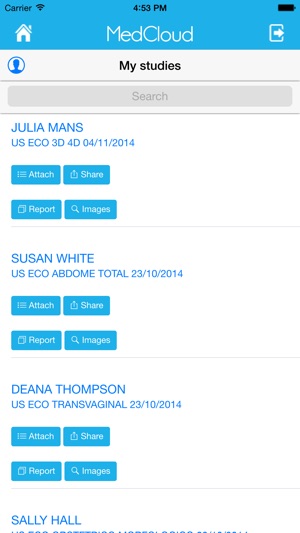

Através de uma plataforma centralizada, integrável e interativa, a MedCloud oferece conectividade e compatibilidade com todos os tipos de mídia, modalidades de exames e protocolos de integração voltados para sistemas de saúde.

Clinicas, hospitais, laboratórios, médicos, dentistas e demais empresas do segmento de saúde podem compartilhar trivialmente seus exames e informações de saúde com profissionais de saúde e pacientes, utilizando apenas uma conexão de Internet como requisito. Médicos, dentistas e pacientes podem interagir e compartilhar seus exames entre si, de forma prática e simples, além receberem opiniões de diferentes profissionais de saúde e manterem seu histórico médico online e seguro.